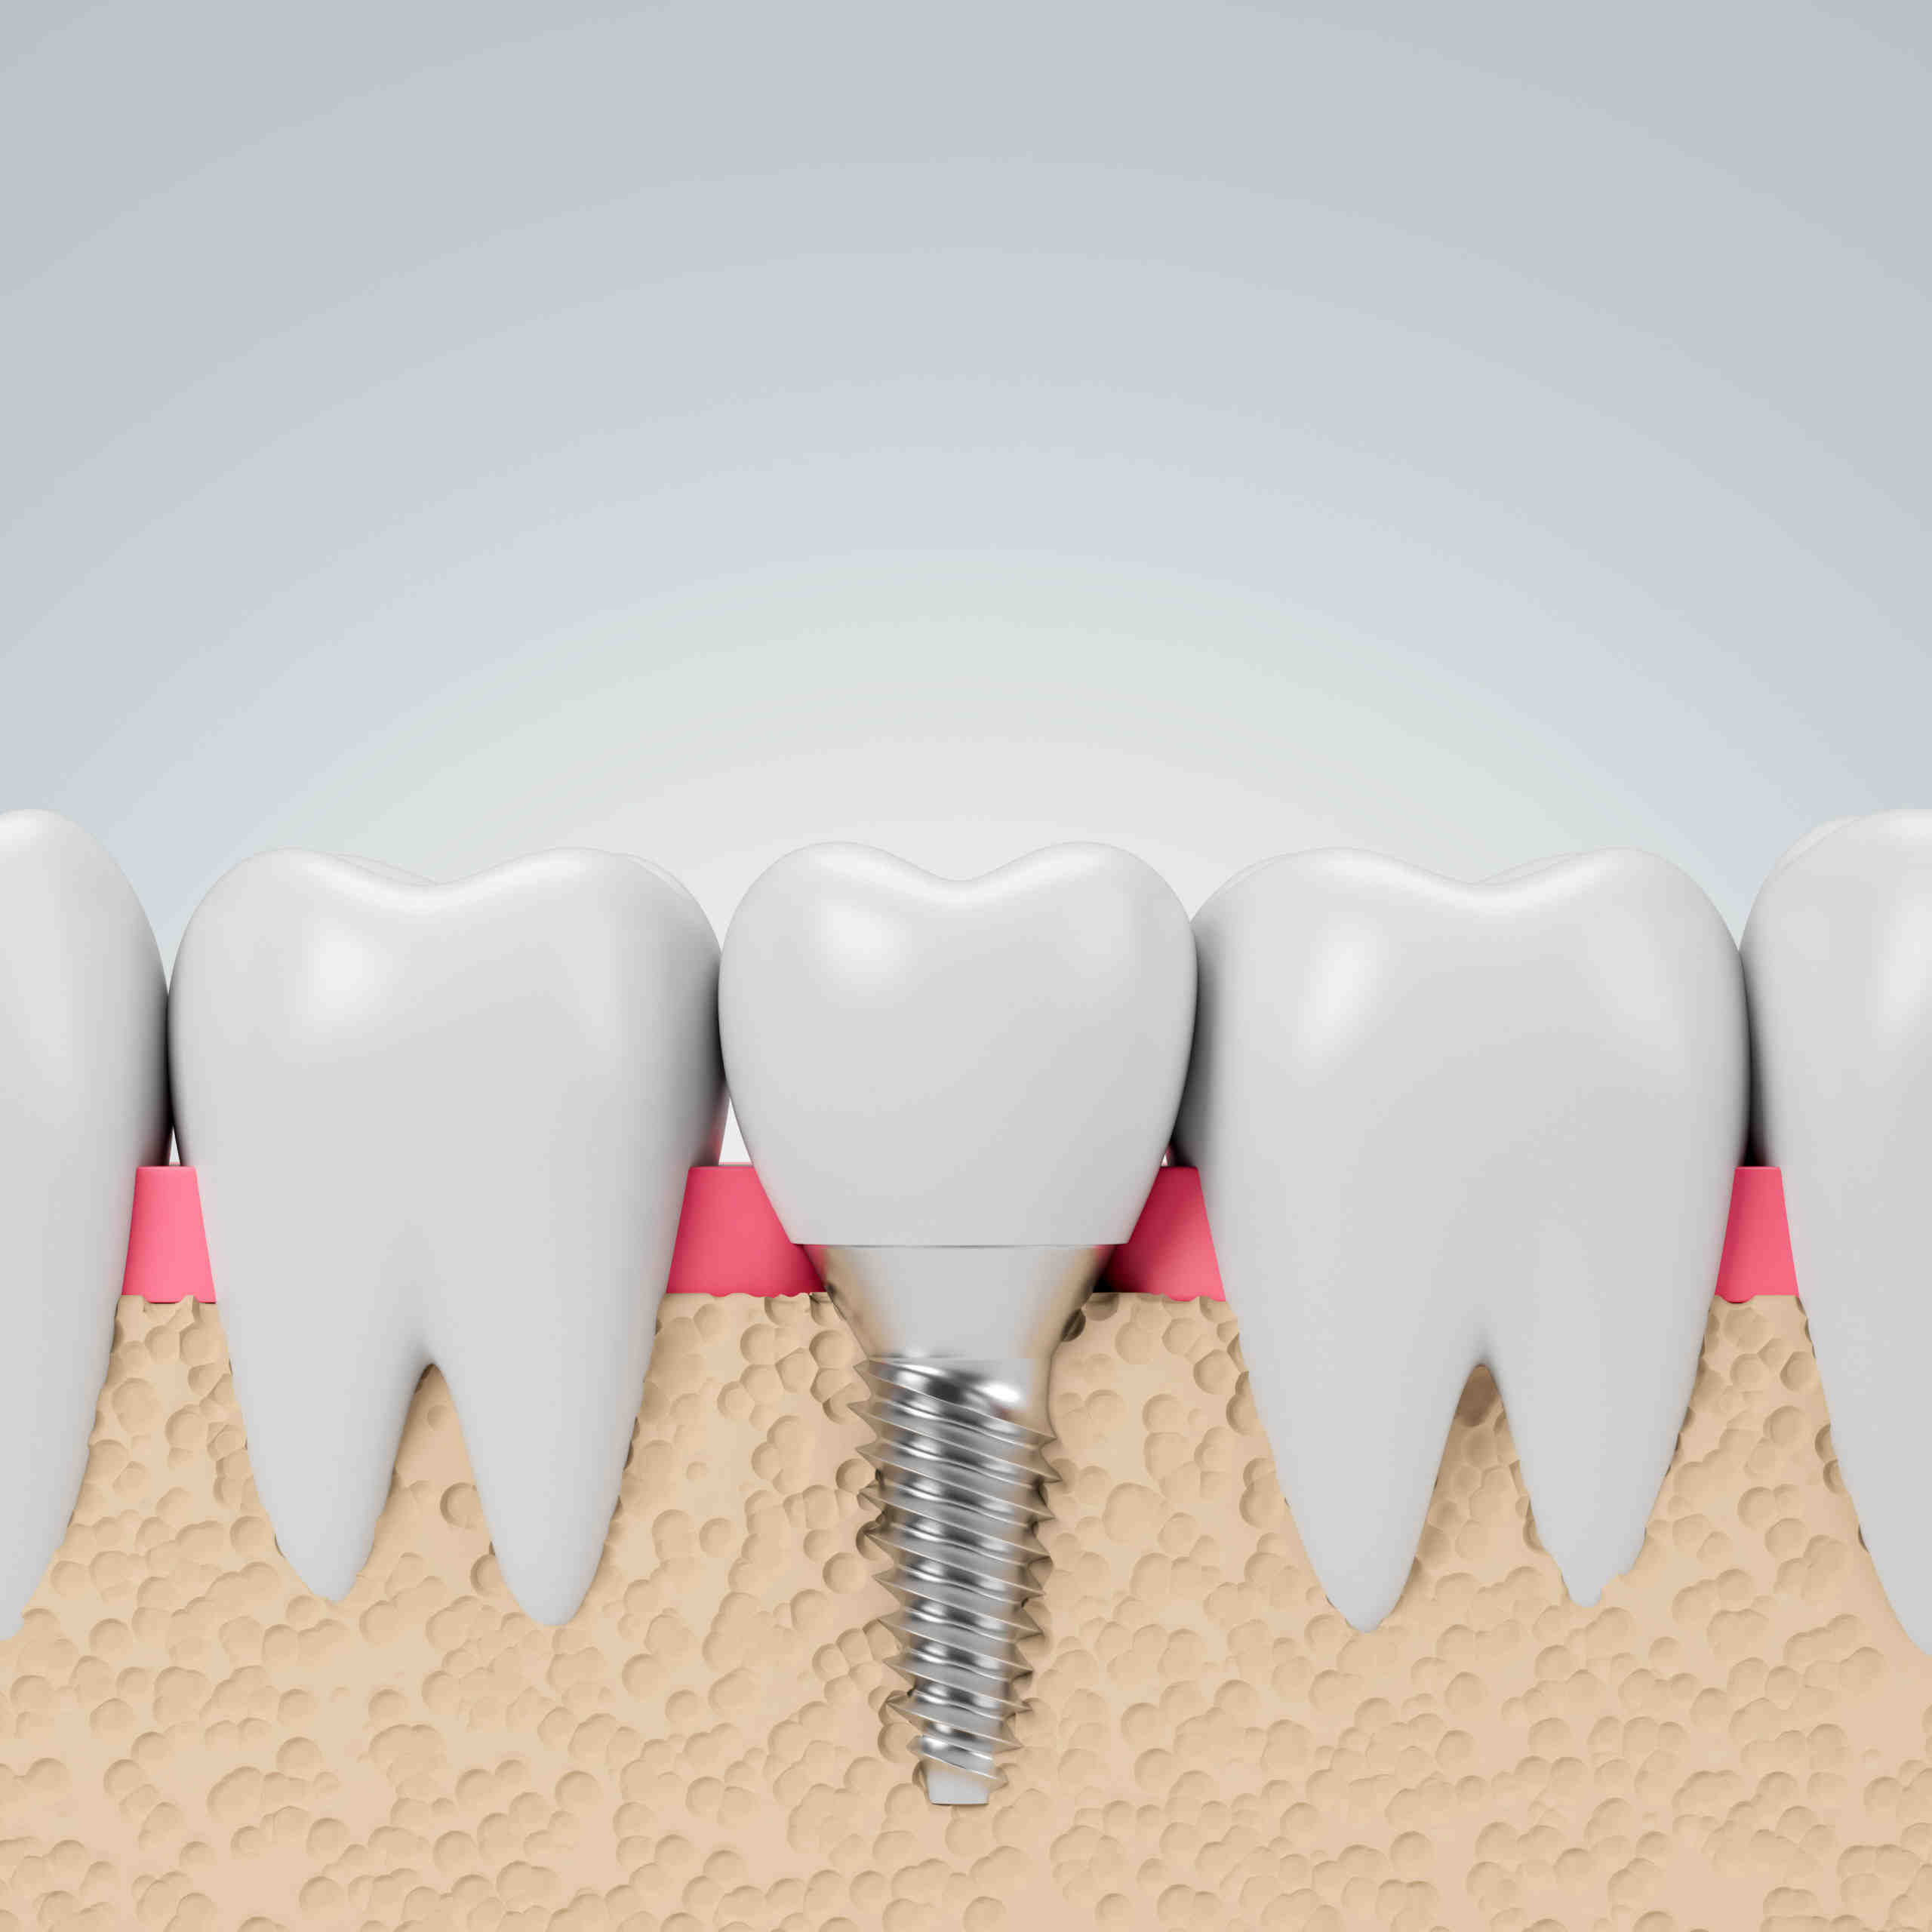

Single And Multiple Teeth Implants Sydney – Ryde | Gladesville | North …

Single Dental Implants in Missoula, MT | Meng Dentistry

Dental Implants Merrick NY | Replace Missing Teeth | Implant Dentist

Dental Implant, Single Tooth

Dental Implants Nashua NH – Natural-looking Tooth Replacements

Discussing: Replacing Missing Teeth With Dental Implants

Front Tooth Implant – AFAM Dental

Front Tooth Implant (Top Rated NYC Dentist) – Midtown & Upper East Side